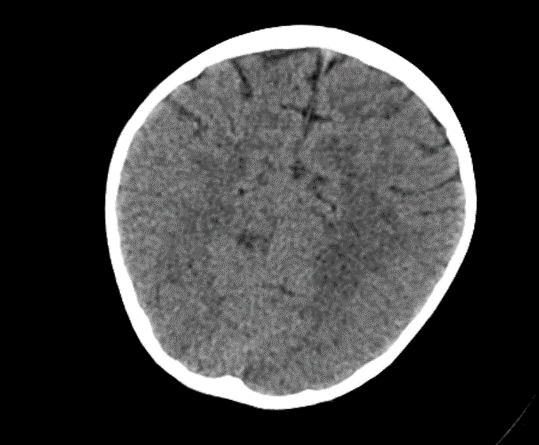

Due to the exacerbation of symptoms and onset of convulsions, a brain CT was conducted, which revealed no significant abnormalities.

Picture1.